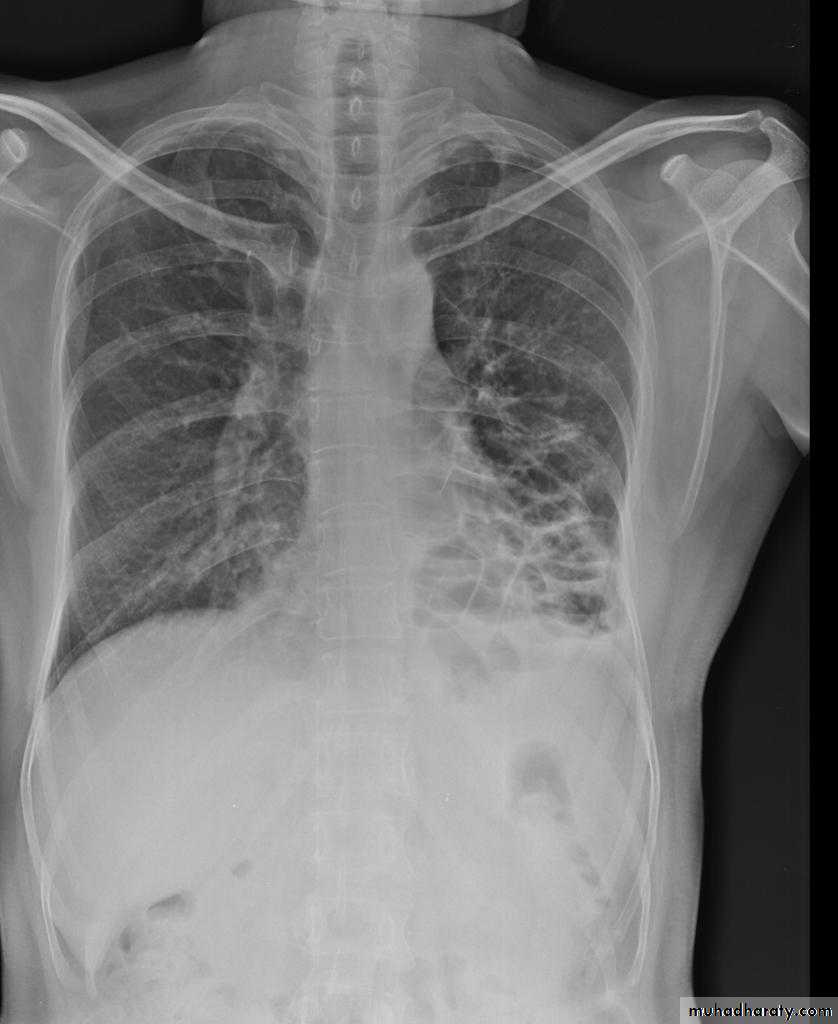

Pulmonary emphysema is defined as the "abnormal permanent enlargement of the airspaces distal to the terminal bronchioles accompanied by destruction of the alveolar wall and without obvious fibrosis". Emphysema is one of the entities grouped together as chronic obstructive pulmonary diseaseRadiographic features

Except in the case of very advanced disease with bulla formation, chest radiography does not image emphysema directly, but rather infers the diagnosis due to associated features :

hyperinflation:

1.flattened hemidiaphragm(s): most reliable sign

2.ncreased and usually irregular radiolucency of the lungs

9.vascular changes paucity of blood vessels ( absent pulmonary markings in outer 1/3 of the lung fields )

10 .pulmonary arterial hypertension

pruning of peripheral vessels

increased calibre of central arteries

right ventricular enlargement

Emphyzema